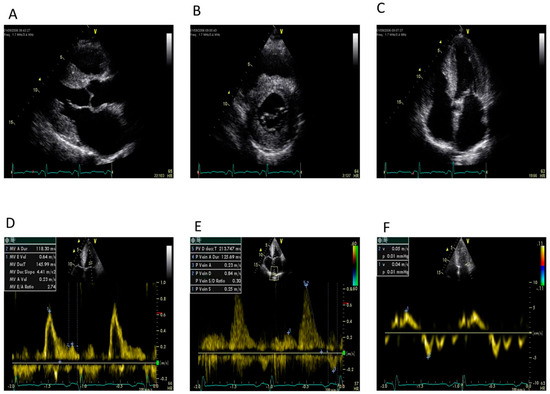

Figure 5.

A positive 99mTc-DPD scan for TTR cardiac amyloid (left) showing uptake in the heart (arrow) and reduced bone uptake. The right-hand panel shows a fused CT/SPECT image showing myocardial uptake, with greater uptake in the septum.